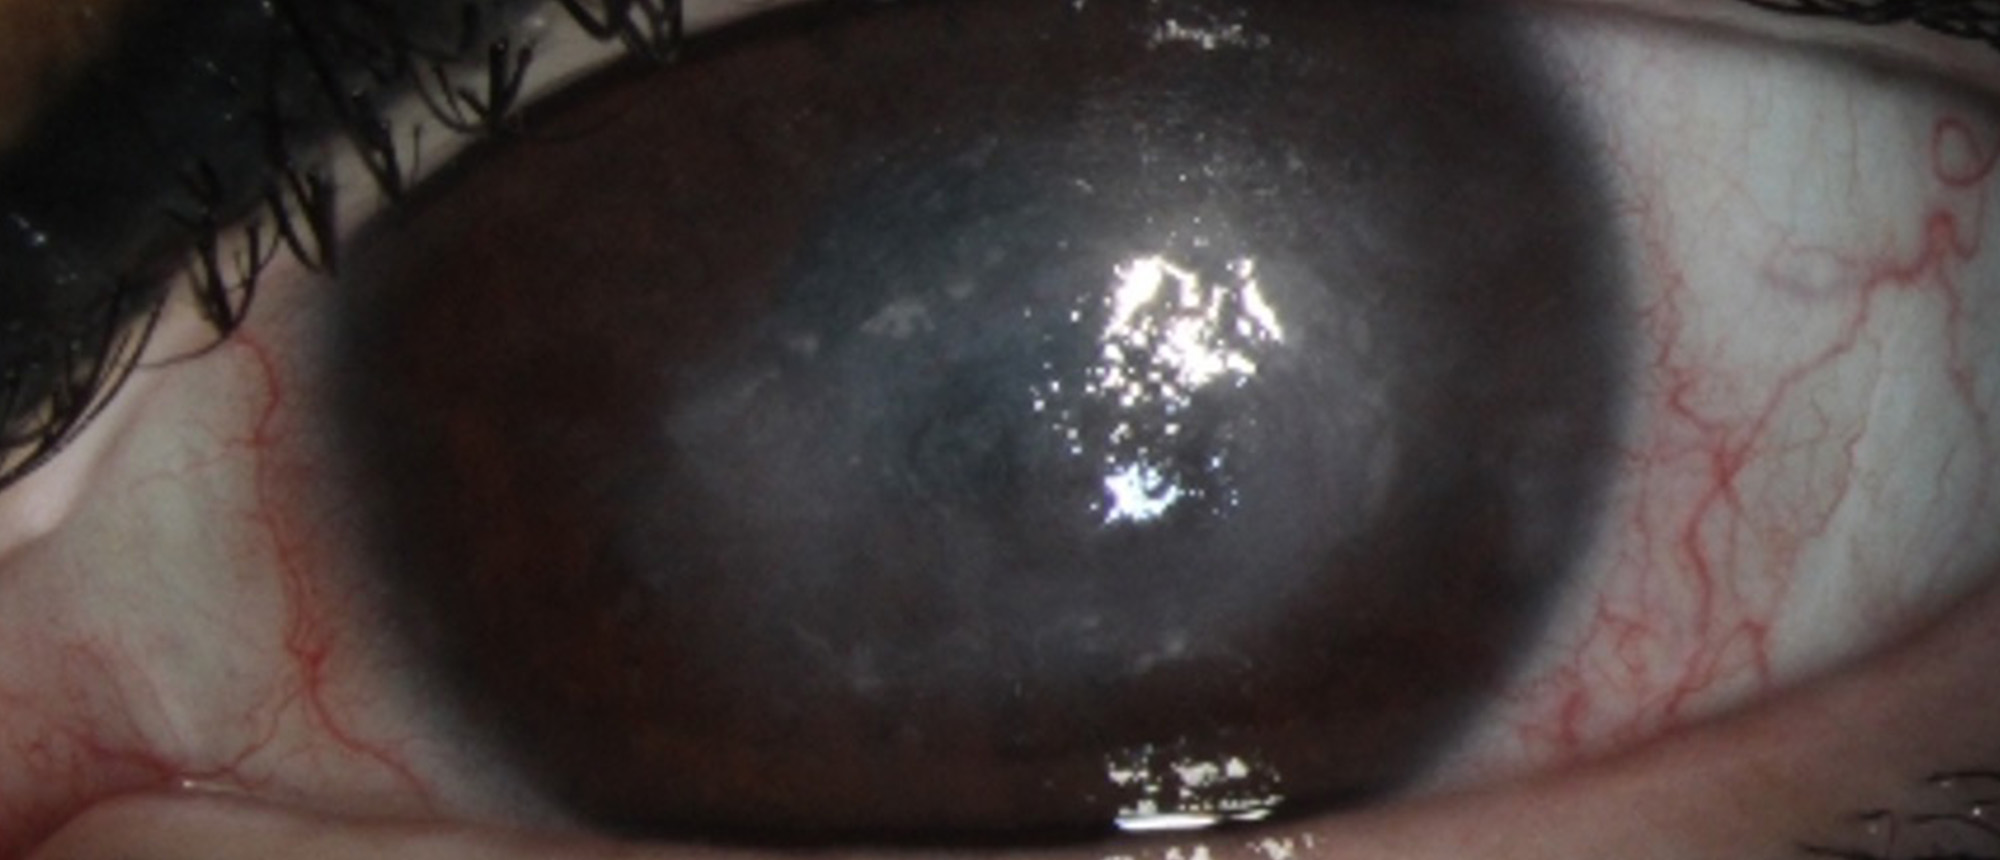

Keratitis Due to Severe Sinonasal Disease with Underlying Granulomatosis with Polyangiitis A young patient with no known prior medical history presents with decreased vision and pain in the right eye. On presentation, patient’s exam was notable for visual acuity of 20/150 in the right eye and 20/…

Abstract A patient presented to the Bascom Palmer General Eye Care Clinic with a progressive decline in her vision in both eyes. The patient was found to have bilateral corneal opacities extending throughout the deep stroma. She underwent genetic testing which confirmed the diagnosis of Granular Co…

Granular Corneal Dystrophy Type II A patient presented to the Bascom Palmer General Eye Care Clinic with a progressive decline in her vision in both eyes. The patient was found to have bilateral corneal opacities extending throughout the deep stroma. She underwent genetic testing which confirmed th…